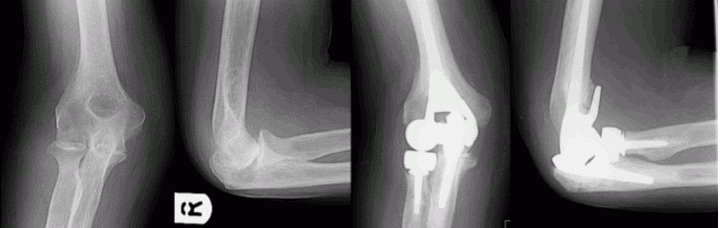

Elbow Replacement

Total elbow replacements can be broadly divided into two categories – unlinked or linked elbow replacement.

Unlinked total elbow replacement

As the name suggests, in an unlinked elbow replacement the two main (humeral and ulnar) components are not linked to each other. An unlinked elbow replacement may be performed in patients with good bone quality and in whom the shape of the joint is well preserved. This type of elbow replacement relies on the native ligaments and well functioning muscles for stability and may reduce the risk of polyethylene wear and thereby prolong the life of the joint.  The radial head may need to be preserved or replaced in an unlinked elbow replacement. Some unlinked elbow replacement designs are convertible and may permit conversion to a linked replacement at a later date without exchanging the implants.

Linked total elbow replacement

In a linked elbow replacement the two main components are linked to each other forming a loose hinge. A linked elbow replacement is chosen when the ligaments are deficient or there is bone loss.